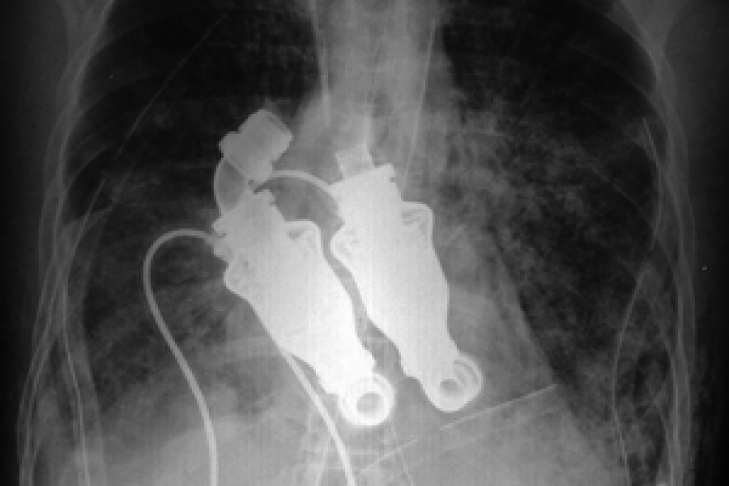

Итак, «сердце» представляет собой два устройства, заменяющие желудочки органа. Суть в том, что аппарат не пульсирует, а вращает кровь в теле в непрерывном потоке. Известно, что имплантирование устройства на себя взяли доктор Билли Кон и доктор О-бад Фрейзер из Техасского института сердца. Мужчина, получивший новое «сердце» находился в состоянии комы. А устройство позволило поддерживать жизнь пациента, пока его почка и печень не разрушились.

Изобретение также протестировали на телятах. Отличительная особенность имплантата заключается в следующем: при прослушивании сердца врачи бы не услышали привычного сердцебиения. Проблема с другими искусственными сердцами заключается в том, что для выполнения аналогичной работы, им приходится биться 100 тысяч раз за день. Отсюда - относительно быстрый износ.

Новое же устройство фактически прокручивает кровь, а не гоняет ее за счет сокращений. Подобная система также позволяет справиться с образованием тромбов и кровотечением, давая больше возможностей для пациентов с прогрессирующей стадией сердечной недостаточности. Ранее у них было всего два выхода: искусственное сердце или запись в список ожидания на трансплантацию органа.